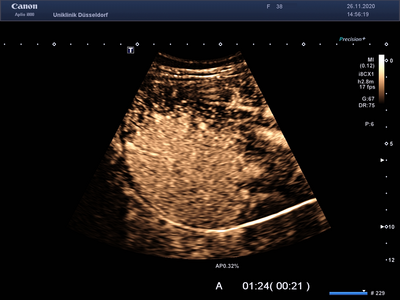

Die Kon­trast­mittelsonographie (KM-Sonographie oder CEUS – contrast enhanced ultrasound) ist ein wichtiges diagnostisches Verfahren, mit dem Tumore der Leber und anderer innerer Organe (z. B. Nieren, Milz, Bauchspeicheldrüse) beurteilt werden können. Neben Tumoren können auch andere Veränderungen dieser Organe charakterisiert werden (z. B. entzündliche Prozesse, Durchblutungsstörungen). Bei erfahrenen Untersuchern hat die KM-Sonographie eine ähnlich hohe Aussagekraft wie eine Computertomographie (CT) oder Magnetresonanztomographie (MRT). Zur Beurteilung von Leberzelltumoren ergänzen sich alle genannten Verfahren (KM-Sonographie, CT und MRT).

Für die KM-Sonographie wird ein Kontrastmittel eingesetzt, welches aus sehr kleinen, von einer Fetthülle umschlossenen, Gasbläschen besteht. Es kommen sehr geringe Mengen (wenige Milliliter) des Kontrastmittels zum Einsatz. Nach der intravenösen Verabreichung verlassen die Gasbläschen den Körper innerhalb weniger Minuten über die Lunge. Die Niere wird dabei nicht belastet, so dass die Untersuchung auch bei Patienten mit fortgeschrittener Nierenerkrankung angewandt werden kann. Unerwünschte Wirkungen (z.B. allergische Reaktionen) treten sehr selten auf und sind unabhängig von bekannten Allergien gegen CT- oder MRT-Kontrastmittel.

Die KM-Sonographie ist nicht nur für die Diagnostik von gutartigen (z.B. Hämangiom, fokale noduläre Hyperplasie - FNH, Adenom) und bösartigen Lebertumoren („Leberkrebs“ oder hepatozelluläres Karzinom - HCC, Gallengangkarzinom oder cholangiozelluläres Karzinom - CCC, Metastasen von Tumoren außerhalb der Leber) und entzündlichen Prozessen (z. B. Abszesse), sondern auch für die Verlaufsbeurteilung dieser Veränderungen hervorragend geeignet.